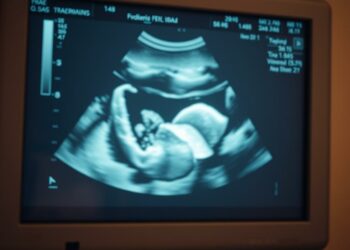

Schlagwort: Ängste in der Schwangerschaft